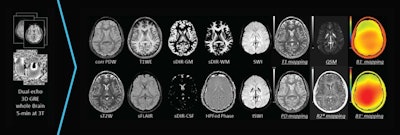

The software allows users to acquire 16 brain contrast images -- including 10 enhanced contrast qualitative outputs and six quantitative outputs -- in five minutes on 3-tesla systems, the company said.

SpinTech's STAGE software is designed for postprocessing of brain images. Image courtesy of SpinTech.STAGE is compatible with most MRI systems, according to the firm, and it is in use at more than 50 hospitals, imaging centers, and research facilities around the world.